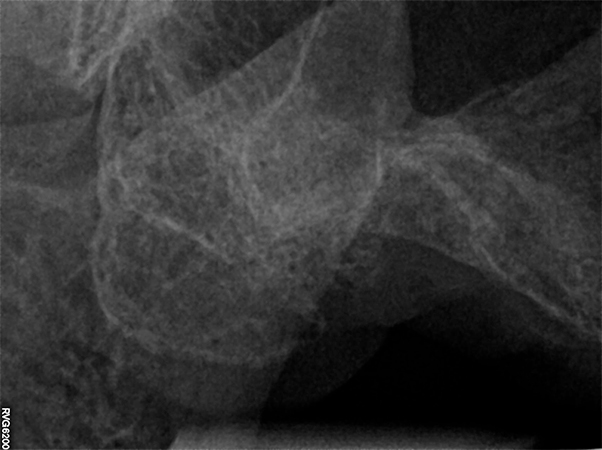

La paziente, di 68 anni, buona salute generale, presentava un grave problema al ponte 17-15-14 con dolore alla masticazione, mobilità e grave perdita ossea su 17 e 12 (Figs. 1, 2, 3).

guarigione in zona Tuber dopo 3 mesi

Fig. 4 - Radiografie iniziali 17, 13, 12 con estrazione del 17 e guarigione in zona Tuber dopo 3 mesi

Una volta atteso 3 mesi di guarigione dei tessuti molli, si procedeva all'esecuzione della TAC mediante repere codificato secondo il protocollo "impression registration" e al posizionamento di una minivite Ustomed in zona 16 per aumentare la precisione del navigatore nella lunga sella edentula distale (Figs. 5, 6, 7, 8).

Guarigione dopo 3 mesi, inserimento minivite Ustomed per inserire repere ed aumentare la precisione del Navigatore in zona edentula. Esecuzione della Cone Beam con repere per il protocollo "instant registration"